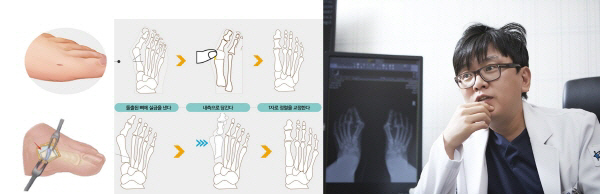

대한족부족관절학회 논문편집위원회 이호진 위원(연세건우병원)은 중기 무지외반증을 외과의 복강경 수술처럼 작은 구멍만을 이용한 최소침습 교정술(MIS)로 치료한다. 절개창이 작아 수술 후 통증 경감 및 절개부위 회복을 위한 치료지연 문제없이 평균 2일 이내 빠른 회복이 가능하다.

말기 및 양측 무지외반증은 단일절개 복합교정술로 동시교정과 빠른 회복이 가능하다. 박의현 위원이 족부전문 SCI 저널 FAI에 게재한 단일절개 복합교정술에 관한 논문에 따르면 고식적 교정술은 이중절개와 연부조직만 봉합한 까닭에 수술 후 통증이 심하고, 재발위험이 높았다.

때문에 박 위원은 단일 절개를 통해 통증과 치료지연 문제를 보완하고, 어떤 장력과 충격에도 정렬이 틀어지지 않도록 돌출된 뼈에 실금을 내어 내측으로 당겨 견고히 고정하는 교정법을 적용했다. 이 결과, 통증을 측정하는 VAS Score(10점 만점)는 7점에서 평균 2점으로 3.5배 감소하였고, 평균 입원기간은 양측 동시교정에도 2.5일로 편측과 큰 차이없이 빠른 회복결과를 보였다.